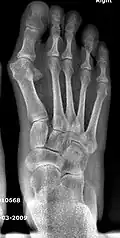

- Second metatarsal stress fracture (Fig. 5)

- Over-correction (Fig. 6)